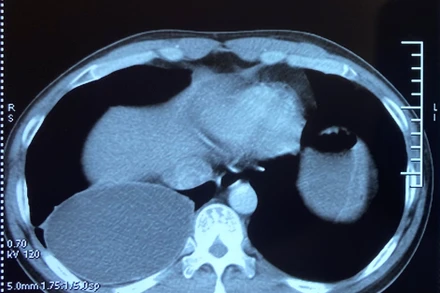

Sau thời gian dài ăn thực phẩm tái và sống, nam bệnh nhân bị nhiễm ấu trùng sán dây chó ký sinh tại phổi. Đây là một trường hợp rất hiếm gặp tại Việt Nam.